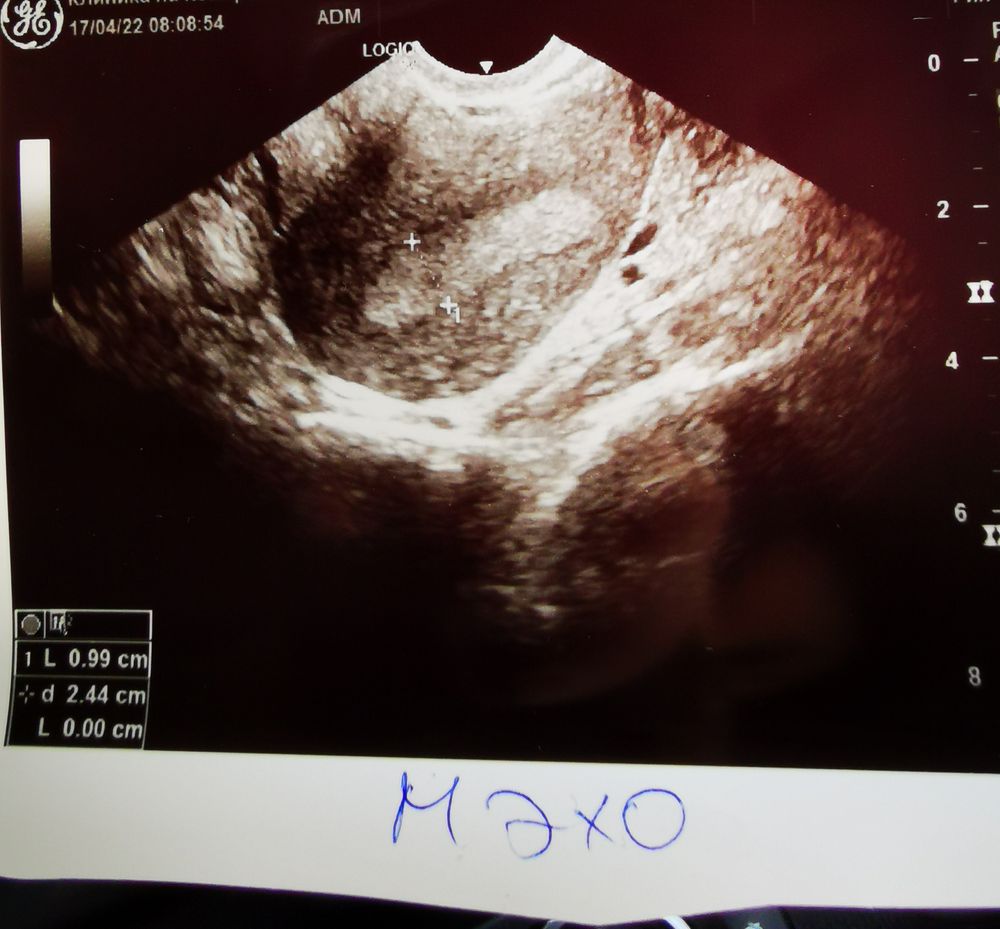

bravo gun, увидела анэхогенное включение в толще эндометрия. Эхогенность не стала проверять, мол рано ещё при таком размере 🤷🏻‍♀️

bravo gun, УЗИ же вот сделали

Елена Л, отрицательный, поэтому и пошла на узи, чтоб глянуть как там эндометрий, потому что в прошлом был очень тонкий. А там такая картина..

Катя, здесь на форуме вычитала, что при таком включении тесты бы точно показывали уже 🥺

Узи пя Помогите расшифровать УЗИ!!!